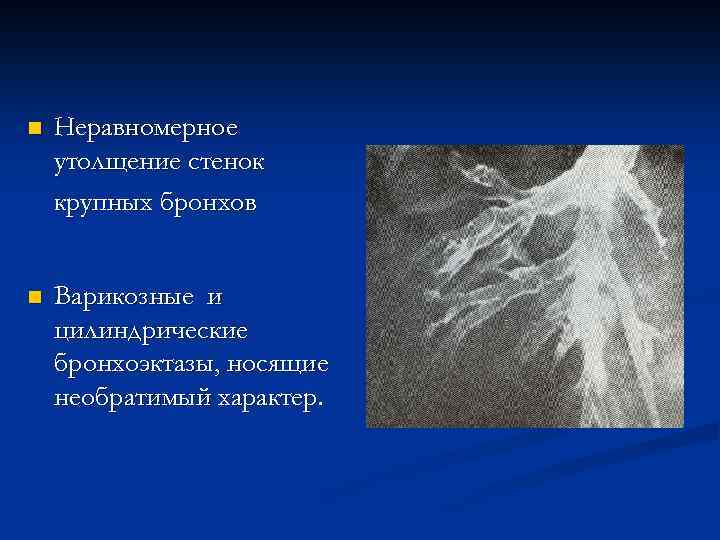

n Неравномерное утолщение стенок крупных бронхов n Варикозные и цилиндрические бронхоэктазы, носящие необратимый характер.